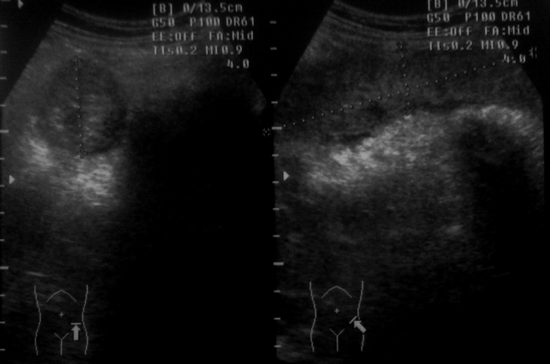

Женщина, 54г. поступила в приемный покой с жалобами на боли внизу живота, кровь при дефекации.

При исследовании в левой подвздошной области по ходу нисходящей ободочной кишки с переходом на сигму резкая болезненность и такая картина:

Симптом поражённого полого органа с вовлечением нисходящей ободочной и сигмовидной кишки. ИМХО может быть Cr либо ЯНЭК. Показана колоноскопия. Сейчас интересный диалог на данную тему активен здесь:http://radiographia.ru/node/5973

Похоже на СППО, надо бы еще толщину стенки измерить...и что там на колоноскопии

Колоноскопия: .... инфильтрация стенок с нарушением просвета на 2/3. Стенки при контакте кровоточат. Закл: Сr н/3 нисходящего отдела ободочной кишки. Взята биопсия.

Ответ: Дистрофичные группы клеток призматического эпителия с признаками вырженной пролиферации и атипией в части клеток.

короче ..рак...наше подозрение на патологию кишечника подтверждено эндоскопически...что еще надо..мысленно себе апплодируем